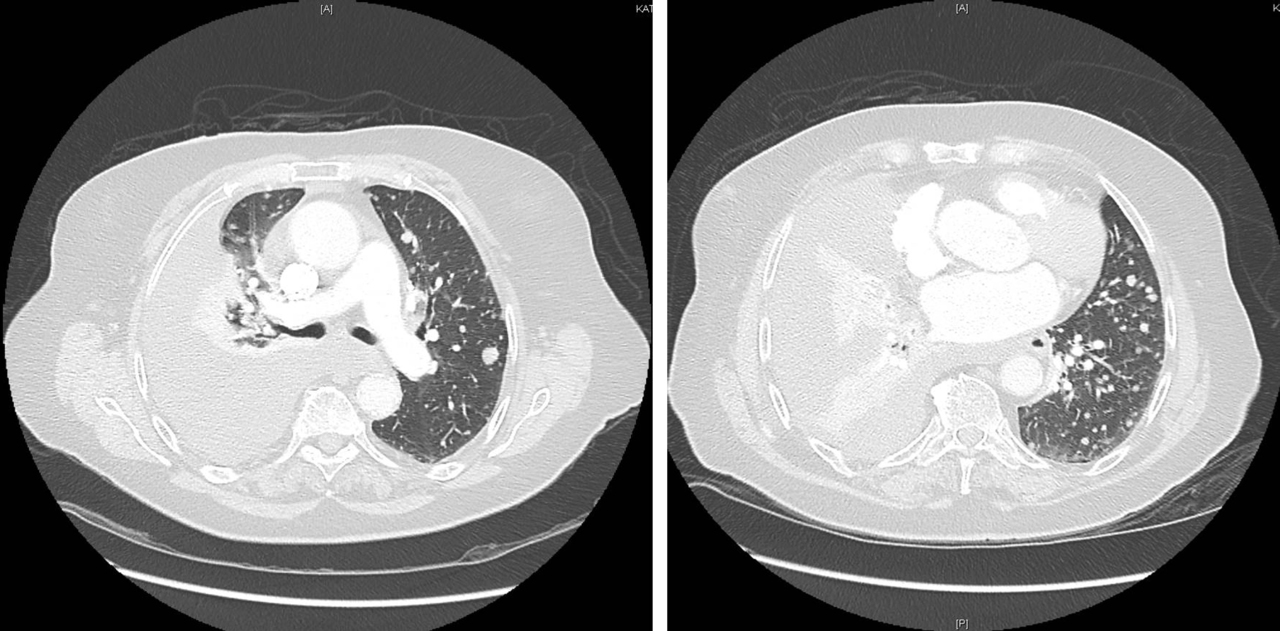

À évoquer en priorité car TVP récente et douleur thoracique. Le traitement anticoagulant en cours n’élimine pas une migration embolique (surtout en cas de mauvaise observance).

À évoquer devant une douleur thoracique latéralisée.

À évoquer devant une douleur thoracique latéralisée chez une patiente avec tabagisme important.